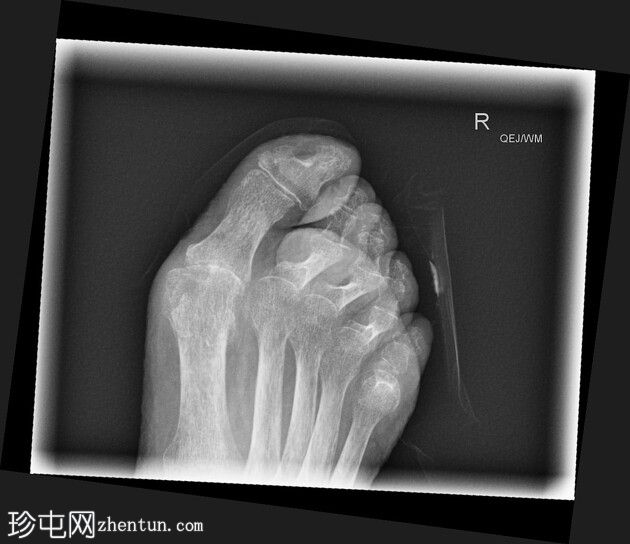

斜位

第二至第五趾跖趾关节明显过伸,近端趾间关节屈曲,符合爪状趾畸形。部分远端趾间关节屈曲程度不及其他关节。